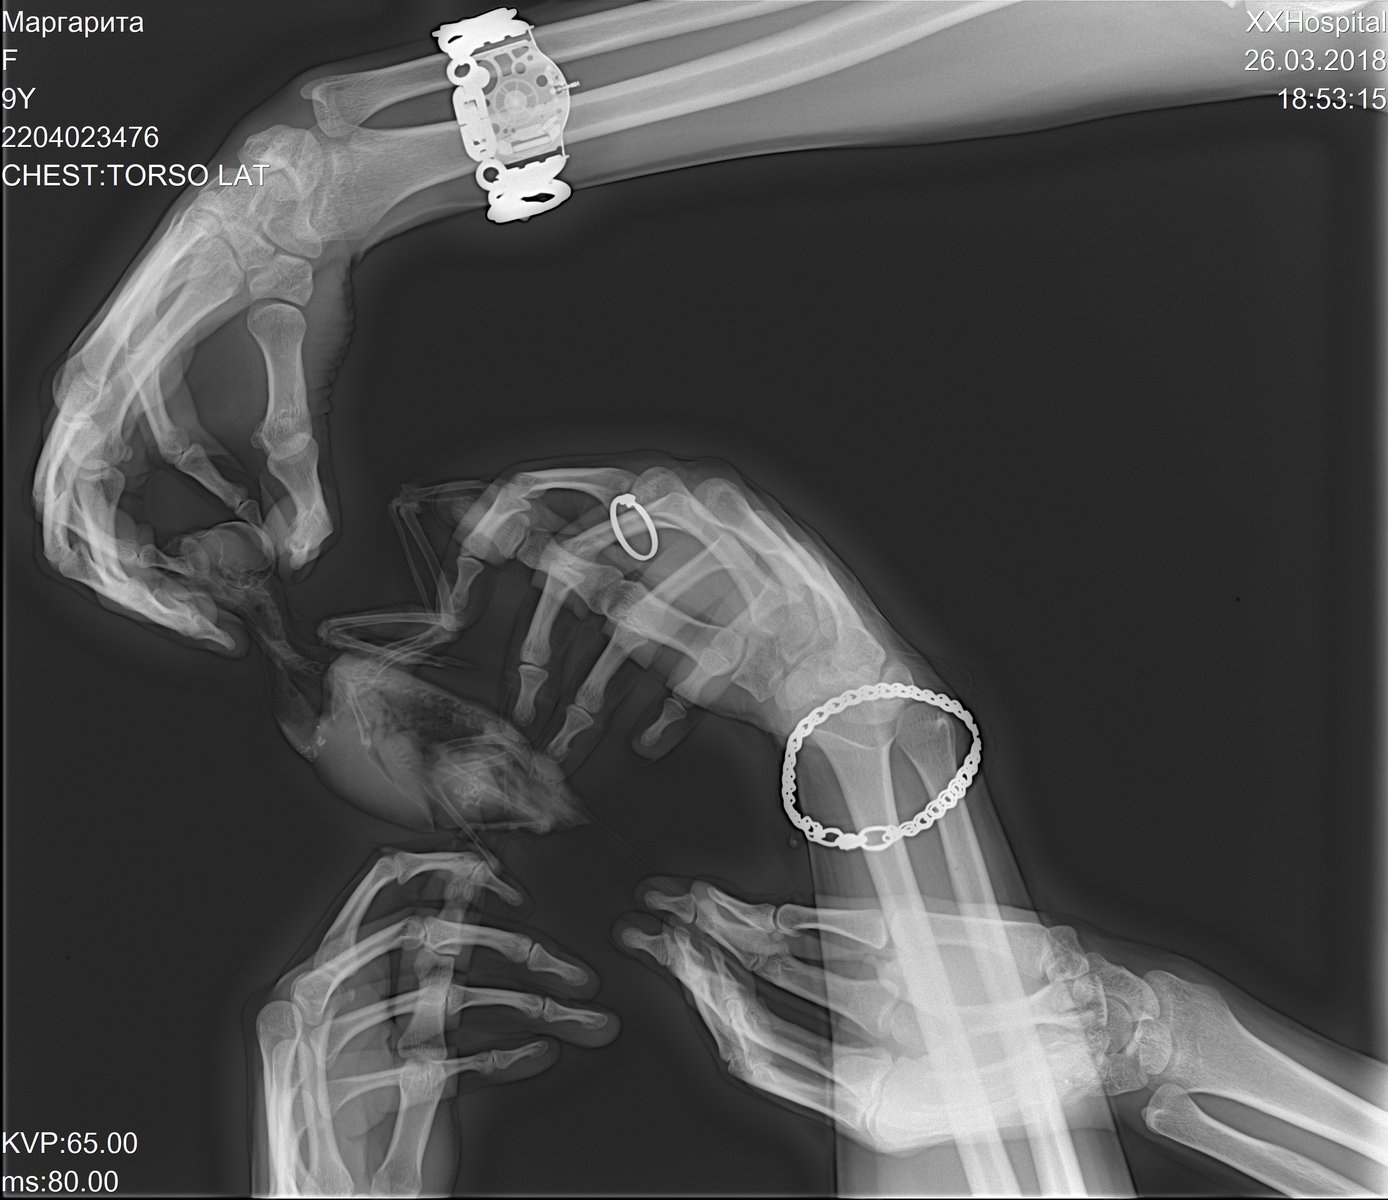

OlgaVoevodina Опубликовано 26 марта, 2018 #94 Опубликовано 26 марта, 2018 Здравствуйте, сегодня ходили на рентген. Корелла, 9 лет. Продолжительное время был синусит, долго лечили. Недавно обнаружили вздутые воздуховодные мешки, решили отвести на осмотр. Врач поставила диагноз грибковая пневмония. Сказала, в худшем случае - аспергиллез. Сказали, взять анализы крови, смывов на бак посев, микологию и цитологию. А так же бронхоскопия/целиоскопия. Но все это под наркозом, в два этапа...Подскажите, пожалуйста, как кореллы переносят наркоз? Птица активная, но чихает, воздуховодные мешки и глазки опухшие. Прилагаю фото рентгена.

Pavel Z Опубликовано 18 марта, 2019 #107 Опубликовано 18 марта, 2019 Я так понимаю, в этой ветке бывают опытные врачи. Хотелось бы проверить диагноз врача по рентгену. И пока я не описал ситуацию и не выложил снимки... мало ли кто прочитает из специалистов. Врач сказала, что нельзя начинать антибактериальную терапию раньше, чем противогрибковую, потому что грибы тут же попрут. Правда? И еще, насколько работают имуномодуляторы и гепапротекторы. Доказан ли эффект? Пеленать жако дважды в день, как я видел сегодня (поначалу было страшно) и вливать ему по несколько лекарств... ведь каждое лекарство вливается несколькими порциями с поглаживанием по горлу птицы и при этом он ворчит вырывается пищит... это испытание. Снимки тут можно выложить?

Pavel Z Опубликовано 18 марта, 2019 #108 Опубликовано 18 марта, 2019 Жако, самец, 6 лет. Прослушивание показывает хрипы при дыхании. Сделали снимки в двух проекциях, клинический анализ помета. Ссылки на снимки прилагаю в конце. По анализу помета, есть вопросы в трех местах: кишечный эпителий +++, лейкоциты - единично, палочки - 30%, остальное в норме. Мазок не бралии странно, не вижу в бумаге диагноза.. На словах Волгина сказала есть основания считать аспергиллез. Назначено: - вифенд 2 раза в день ГОД (!!!) - или тербинафин с подбором дозировки 2 раза в день ГОД (!!!) - суммамед суспензия 2 раза в день, 30 дней - Гептрал 1 раз в день год - Иммунофан 1 раз в день (не привожу описаний приготовления, дозировки, вспомогательное) Вопросы: - где на снимке видны проблемы и можно ли сказать что четко аспер? - действительно ли нельзя начинать антибактериальную терапию до антигрибковой? (грибы начинают быстро расти?) - много шансов на излечение в принципе? (лечить буду конечно!) - насколько эффективны эти гепатопротекторы и иммуностимуляторы? (я видел и пробовал эту процедуру вылова птички, пеленания, захвата головы, вливания шприцем по частям с поглаживанием - это надо долго держать будет...) - слышал подделывают вориконазол - были случаи? Снимки https://mega.nz/#!bNowDCYC!6jfCV5Htlnw6TsVnuddn2HVlJTpmqiMC5_91X-49pIs https://mega.nz/#!ychAHIwA!bb0yDuZcFyLwMQ2YnHYPdKxxWpO0RVnRx_5Rp11UgqY

Pavel Z Опубликовано 19 марта, 2019 #114 Опубликовано 19 марта, 2019 Надо было просить описание снимков, хотя может врач и сделала, я позвоню. Мне знающие люди указали куда смотреть. На снимках в подключичных мешках есть гранулемы и совсем чуть чуть какие то вкрапления в правом легком. Чтобы сказать точно, что это аспер, нужно сделать мазок. Странно, что такой специалист как Волгина С.В. об этом не сказала ровным счетом ничего. Но ясно точно, что нужна антибактериальная терапия и проводить ее нужно с антимикотиком. И тут очень важный вопрос, в виду ДИКОЙ стоимости вориконазола в сочетании с вероятностью купить подделку: можно ли провести а\б с тербинафином и по результатам принять решение о вориконазоле? Антибактериальная нужна, хрипы при дыхании при прослушивании врачом. До Волгиной тоже попробую достучаться сегодня.